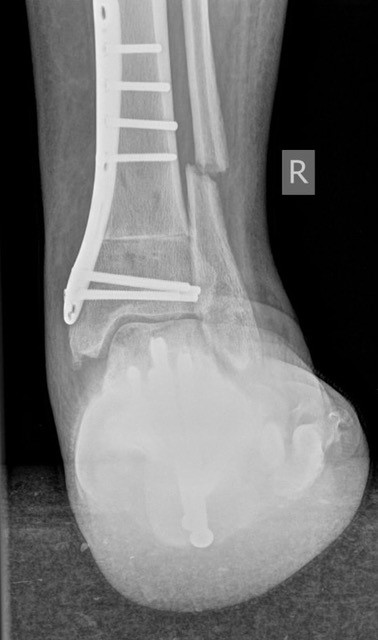

• Fuß belastet dp und seitlich (Abb. 14 und 15)

• Saltzman view (Abb. 16)

Zum Lesen der Bildbeschreibung und zur Vollansicht bitte die Bilder anklicken. Bilder: A. Simon

Typische Merkmale des Saltzman View

• Calcaneus steht varisch zur Tibialängsachse

• Der erste Zehenstrahl ist medial erkennbar

• Konsekutive varische Gelenklinie des oberen Sprunggelenkes